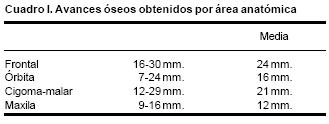

Luego de un periodo de latencia de cinco días, los distractores se activan a un ritmo de un milímetro cada día. Los avances obtenidos en este grupo de pacientes varían entre 16 y 30 mm, en el hueso frontal, de 12 a 25 mm, en el complejo órbito–malar–cigoma y de 10 a 18mm, en el maxilar. Luego de un periodo de consolidación de 10 a 12 semanas, los distractores óseos se retiran bajo sedación.

En todos los pacientes se logró el avance planificado de los segmentos óseos, al corregir la deformidad del hueso frontal, el exorbitismo y en la retrusión del tercio medio en los casos con avance en monobloque. Los avances mayores se obtuvieron en el hueso frontal y variaron entre 16 y 30 mm., mientras que los menores fueron los del hueso maxilar que fluctuaron entre 9 y 16 mm. (Cuadro I). Radiológicamente los controles postoperatorios tempranos mostraron inicialmente áreas de hipodensidad ósea, que al final del periodo de consolidación cambiaron a áreas de densidad ósea radiológica normal, lo que significa neoformación de hueso. Las áreas de hueso neoformadas que consolidaron en forma más rápida, son las ubicadas en las líneas de osteotomía de la unión pterigomaxilar, pared lateral de la órbita y unión frontoorbitaria. Las áreas que más tardaron en consolidar incluye la porción lateral y superior del hueso frontal.